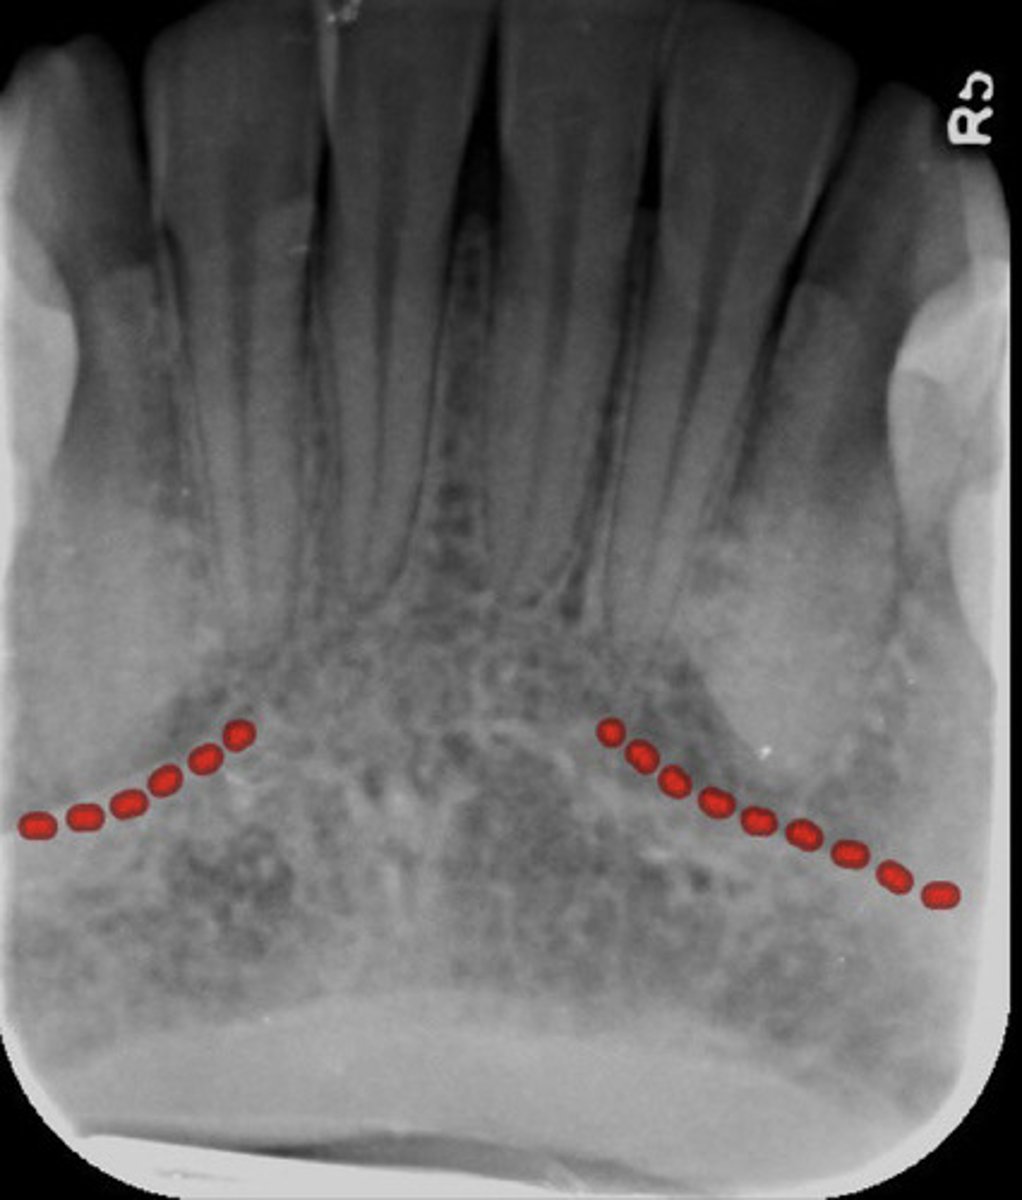

What is the lingual foramen?

What does the lingual foramen look like radiographically?

INFOrmation on lingual foramen

radiolucent & in the mandible srrouned on genial tubercules

What are genial tubercles?

information genial tubercules

inferior to mandibular incisors & radiopaque

What do genial tubercles look like radiographically?